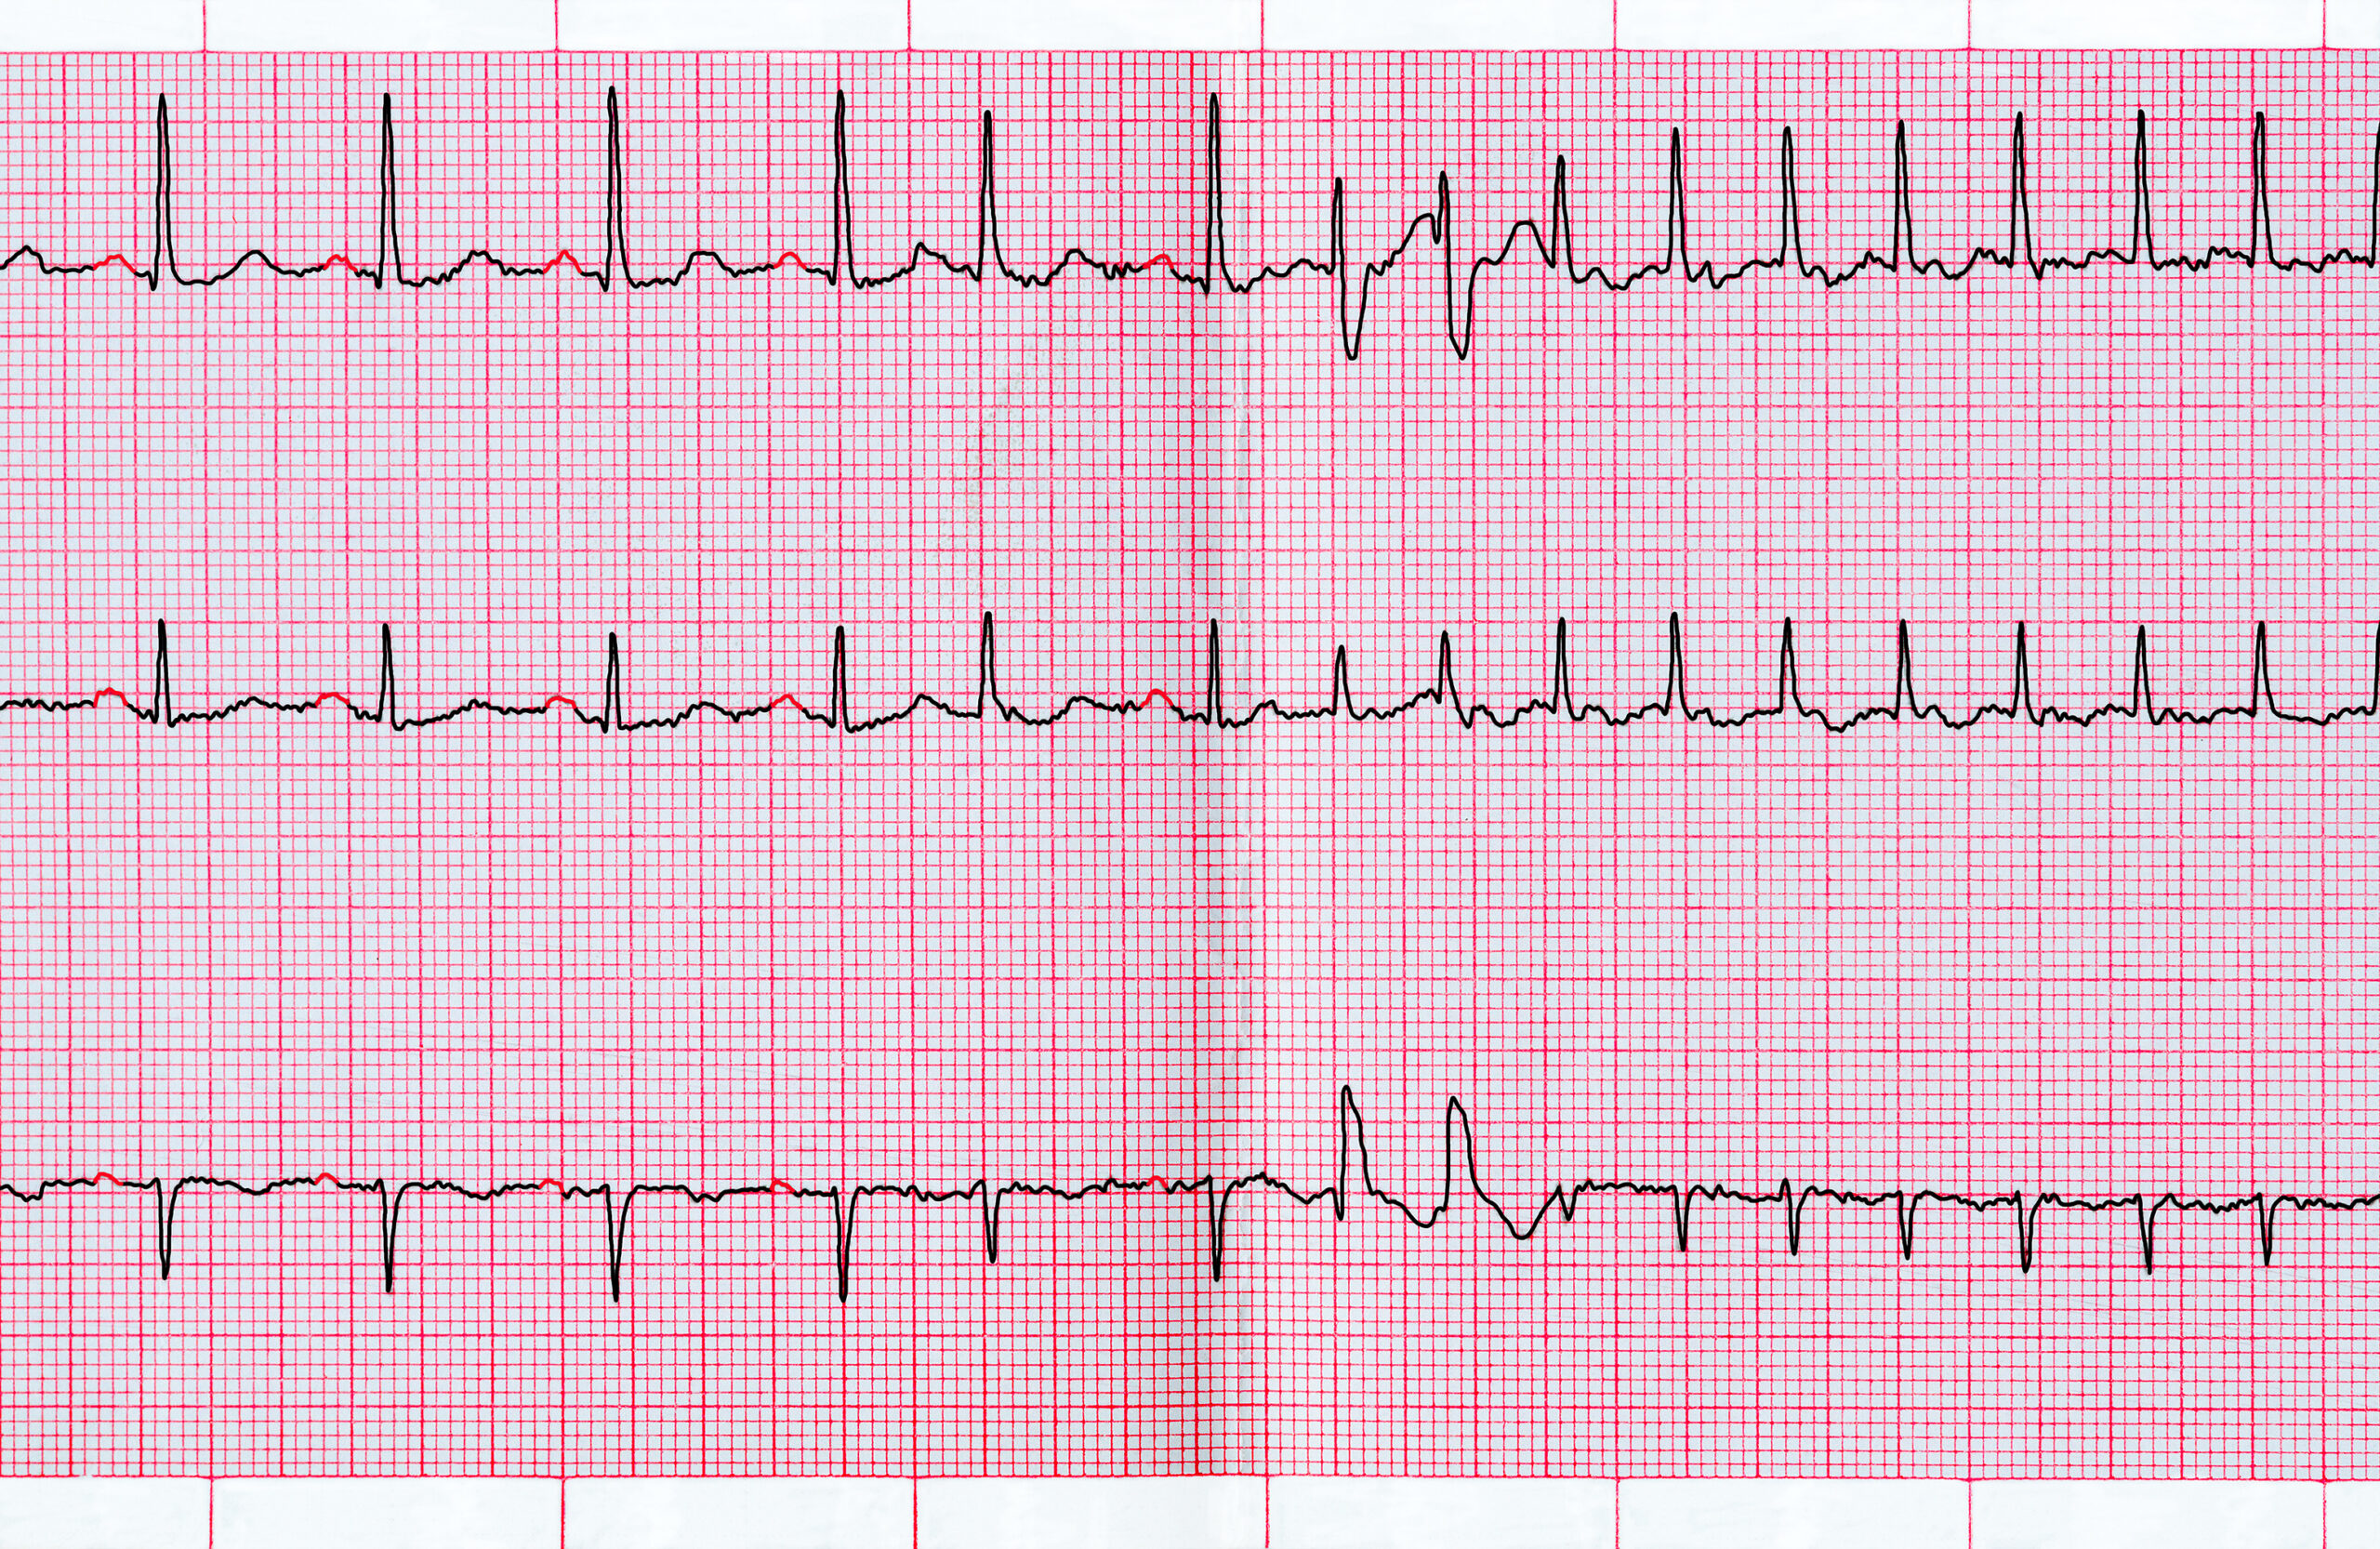

In the DECAAF II randomized controlled trial, researchers evaluated the safety and efficacy of using magnetic resonance ...

Researchers led by Karl Georg Haeusler investigated the incidence of ischemic brain lesions via magnetic resonance ...

A new study shows that intracardiac echocardiography (ICE) and its integration into three dimensional (3D) ...